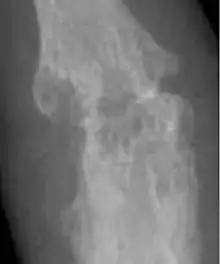

| 患有類風濕性關節炎的手,這種關節炎屬於自體免疫疾病 | |